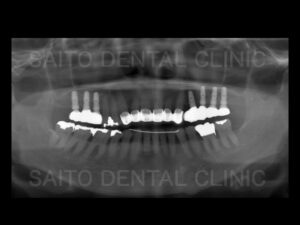

治療前と治療後の状態です 出っ歯や歯の隙間の改善と奥歯が噛めるようになり満足していただけました

左下の欠損していた部分もインプラントやブリッジを使用することなく矯正治療によって隙間を

なくすことができて費用も抑えることができました